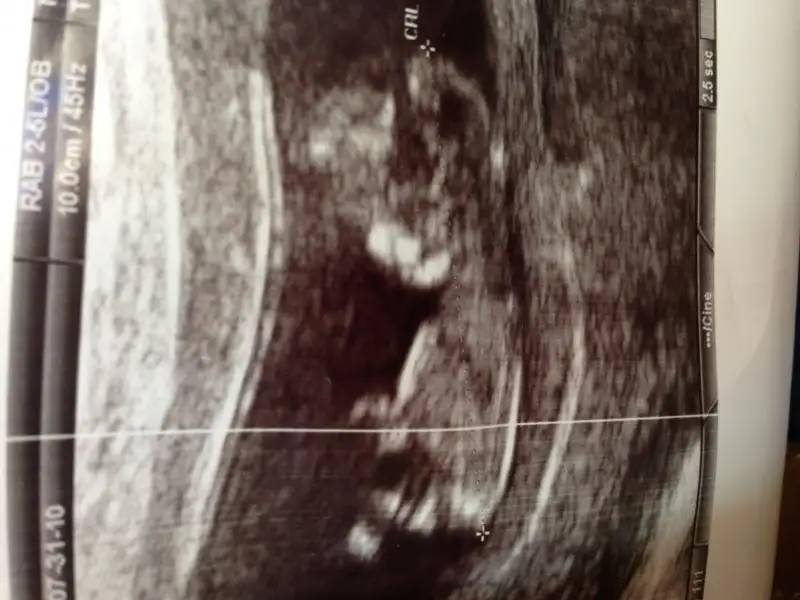

dr soylemeden siz gorun genital nub teorisi ( bebegin cinsiyeti)

bendeeee...bizim de babacı bir kızımız var..anneci bi oğlum olsun ne kadar çok isterdim...ben bebişin nubunu ekranda gördüm.doktor bize önce kız dedi.sonra 'bakın beyefendiciğim bi çıkıntı var erkekte olabilir' dedi ve bi çıkıntı gösterdi ama paralel miydi dik miydi anlamadım.heycandan fotoğrafını da istemedim...